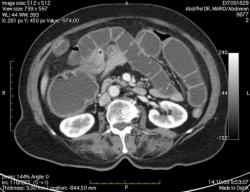

КТ брюшной полости. Женщина 73 года с жалобами на запоры.

Пациентка женщина 73 года. Предъявляет жалобы на запоры, спастические боли в брюшной полости.

ИзображениеЦиркулярное сужение в поперечной ободочной кишке. Ни это ли причина проблемм?

Новообразование в среднем отделе поперечной ободочной кишки с циркулярным сужением просвета и хронической механической толстокишечной непроходимостью. Признаков метастазирования в данной анатомической области не обнаружено. Пациент безусловно нуждается в хирургическом лечении.

Я не занимаюсь КТ, но сам характер сужения толстой кишки как-то вызывает сомнения, ракового ли он характера? Сужение то циркулярное, но больно уж ровненькое и нет признаков инфильтрации вокруг (хотя рак, конечно может иметь и такой вид). Ну, думаю dr.Mario со временем откроет карты и будет дана гистология.

Циркулярная стенозирующая опухоль (аденокарцнома) толстого кишечника; с типичной КТ презентацией и признаками обструкции. Пациентка была оперирована на второй день после КТ.